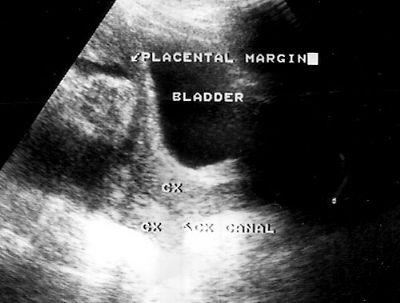

Normal placentation without previa.

Posterior placenta previa.- Placenta/Cord Insertion/Cervix/Fluid